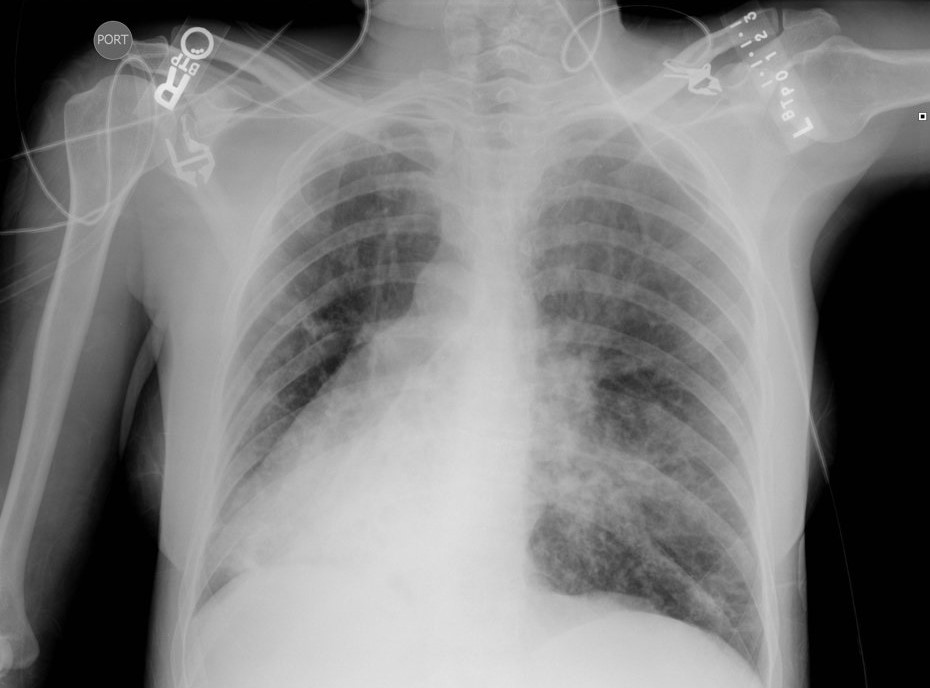

Pomerne často sa u chorých s Kartagenerovým syndrómom vyskytuje stav nazývaný po latinsky ako „situs viscerum inversus“ (obrátené umiestnenie vnútorných orgánov). Chorý s touto zvláštnosťou má srdce na pravom mieste (doslova). Pečeň a žlčník sú u takého človeka vľavo, slezina s žalúdkom naopak vpravo. Tento stav sa môže vyskytovať aj samostatne bez Kartagenerovaho syndrómu a sám o sebe veľmi často uniká pozornosti. Postihnutý človek nemáva žiadne ťažkosti (niekedy však môžu byť prítomné srdcové chyby) a celý stav sa zistí náhodne pri starostlivom vyšetrení.